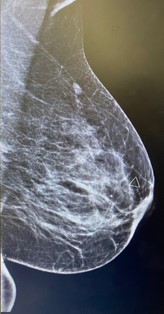

Left breast and axilla ultrasound and Mammogram showed: Left breast palpable lesion with architectural distortion in the upper lateral mid/anterior third at 3:00, It measures 0.9 cm and seen with no significant vascularity. A clip was placed.

Figure 1: Left mammographic views ML of the left breast showing an irregular, spiculated, high-density mass in the upper outer quadrant. The lesion causes architectural distortion without associated calcifications. Findings are consistent with desmoid-type fibromatosis confirmed on histology.

Mammography presents irregular walled and highly dense lesion with no calcifications mimicking sometimes breast carcinoma [6].

Radiologic evaluation of our case revealed soft tissue mass inducing architectural distortion.